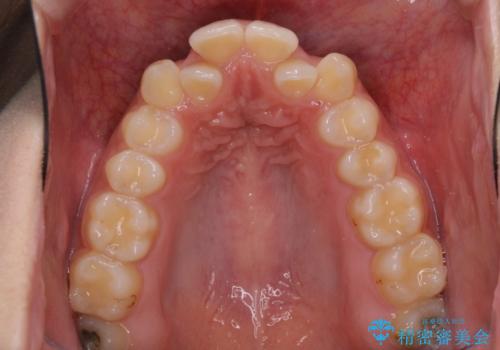

骨格的に左右にずれいている 前歯のデコボコをインビザラインで解消

- 前歯のデコボコと八重歯を気にして来院された患者様です。

叢生の程度は中等度であったため、IPR(歯と歯の間を削る)と歯列の側方拡大をメインに、インビザラインを用いて歯列を改善することとしました。

また、下顎骨の右側変位による右側臼歯の咬合を改善させるよう試みることとしました。

右側の咬合改善を目標に様々な手法を用いましたが、骨格的なズレによる不正咬合はインビザラインでは改善することができませんでした。